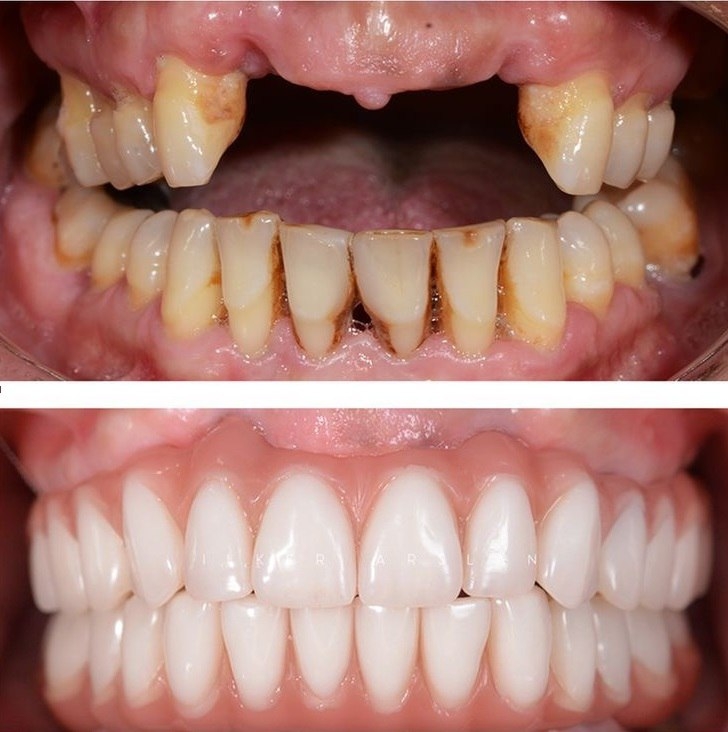

/ 5

В стоматологическом центре “5 Принципов” в Симферополе мы предлагаем качественное протезирование, которое возвращает не только полноценную функцию зубного ряда, но и уверенную улыбку. Наши специалисты подбирают индивидуальные решения под каждого пациента: затемнение участка, восстановление зубов, подбор материалов и форм, максимально близких к природной эмалированной структуре. Мы уделяем особое внимание деталям: точная примерка, правильная окклюзия и гармония с соседними зубами. В арсенале клиники современные технологии — CAD/CAM системами мы проектируем протезы на основе цифровых снимков, что обеспечивает точность посадки и ускоряет сроки изготовления. Виды протезирования, которыми мы гордимся, включают металлокерамические и керамические коронки, мосты и частичные съемные протезы, а также имплантаты в сочетании с фиксированными конструкциями. В “5 Принципах” акцент ставится на функциональность, эстетику и долговечность. Мы тратим время на тщательную консультацию: обсуждаем форму, цвет и стиль улыбки, чтобы результат гармонировал с лицом и возрастом пациента. Используем биосовместимые материалы, снижаем риск аллергических реакций и повышаем комфорт. Пациенты в Симферополе доверяют нам, потому что видят естественную улыбку, улучшение жевательной функции и уверенность в себе. Запишитесь на консультацию и убедитесь, как протезирование в нашем центре может изменить вашу улыбку к лучшему.